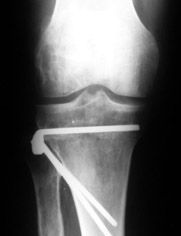

Mangal Parihar 11 Сентябрь 2005, 11:28

|

Alex,

I do upper tibial osteotomies with either an ilizarov fixator and acute correction of the deformity or with an orthofix with gradual correction.

Sending you pics of the steps of the osteotomy and the frame.

You can do the osteotomy in a "focal dome" or in a transverse fashion. The dome has the advantage of having a good contact, allowing weight bearing as tolerated early on.

The level is below the tibial tuberosity.

The frame I use is pretty simple, with one wire each in the proximal and distal ring, two schanz pins in the proximal ring, and one each in the middle and distal ring.

I preconstruct a frame with the proximal ring in varus by the use of coupled washers in the threaded rods in the front and back. These are used as hinges, and after the correction, a medial and lateral threaded rod is also added.

Since the center of rotation of these deformities is usually near the knee joint line, lateral translation of the distal fragment is necessary to normalise all the axes.

You can also do the osteotomy in a transverse fashion.

When I use an orthofix fixator, the osteotomy is oblique, starting below the tuberosity and ending 1 cm away from the lateral cortex at the level of the head of the fibula. No fibular osteotomy is needed there. The deformity is gradually corrected over 2 or three weeks.

You could also do the same with an ilizarov fixator

Regards

Mangal Parihar

Отправитель: Alexander Artemiev 11 Сентябрь 2005, 14:55

Приветствую.

MP> I do upper tibial osteotomies with either an ilizarov fixator and

MP> acute correction of the deformity or with an orthofix with gradual

MP> correction.

Посмотрел я картинки:(

Это не эстетика.

Это рубка леса и лучевая болезнь.

С уважением Александр Артемьев